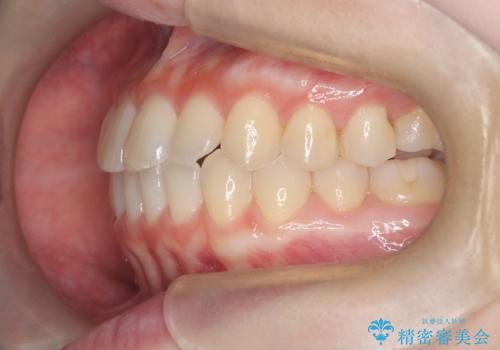

前歯と奥歯のガタガタを矯正で改善

- 患者様は、前歯と奥歯のガタガタ(叢生)を改善し、正面から見た時の歯並びを美しく整えたいとのご要望で来院されました。診断の結果、非抜歯での矯正が可能と判断し、インビザラインを使用する治療計画を立案しました。透明な矯正装置で目立ちにくい治療を行いながら、前歯と奥歯の両方を整列させることを目標にしました。

インビザラインを用いて、前歯の見た目を重視しつつ、奥歯のガタガタも改善しました。特に正面から見た際の美しい歯列を意識し、段階的に歯を移動させることで、全体の調和を図りました。治療中は、適切な装着時間を守ることや、装置の清潔を保つことが重要でした。また、歯肉や歯列全体に無理な負担がかからないように移動を管理しながら治療を進めました。結果として、前歯と奥歯がきれいに並び、見た目にも機能的にも満足いただける仕上がりとなりました。